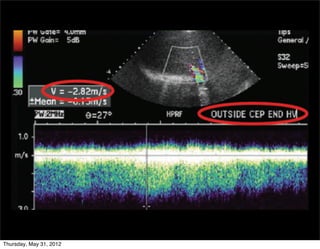

Flujo hepatofugo

• Definición: Flujo que se ALEJA del hígado

Importante en:

1. Diagnóstico HP

2. Conocer permeabilidad de

shunt portosistémico

3. Px hepatópatas

4. Seleccionar pacientes NO

candidatos a

• Quimioembolización

intraarterial

• Portografía arterial por

TC

incich/grupo ct scanner                       Departamento de Radiología/Unidad PET-CT

SIEMPRE demostrar en la misma

• Portografía arterial por   imagen el flujo petal de la arteria

TC                               con el fugo portal